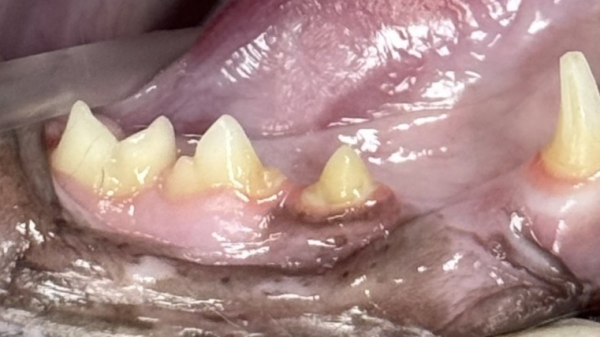

5살 러시안블루 고양이가 내원했습니다.

러시안블루 보호자님은 양치 중

발갛게 보이는 치아를 보고 염증으로 생각하셨고,

더 열심히 양치를 해주셨습니다.

하지만 고양이는 양치할 때마다

아파하는 반응을 보여 병원을 찾게 되셨는데요.

진료 중 확인해보니 고양이는 치석과 치은염이 있었고,

육안상으로도 307번 치아에

치아흡수병변이 의심되어,

발치 가능성과 함께 치과 방사선 촬영과

스케일링을 예약해드렸습니다.